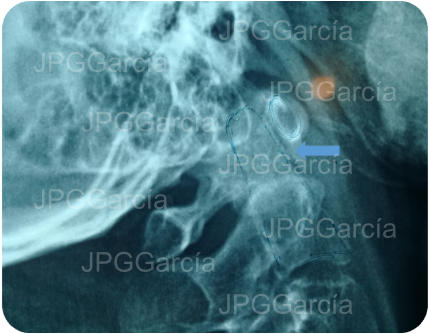

Imágenes de tomografía de con realce metálico que muestra el postquirúrgico a la fijación C1 C3 más remoción del arco posterior del atlas